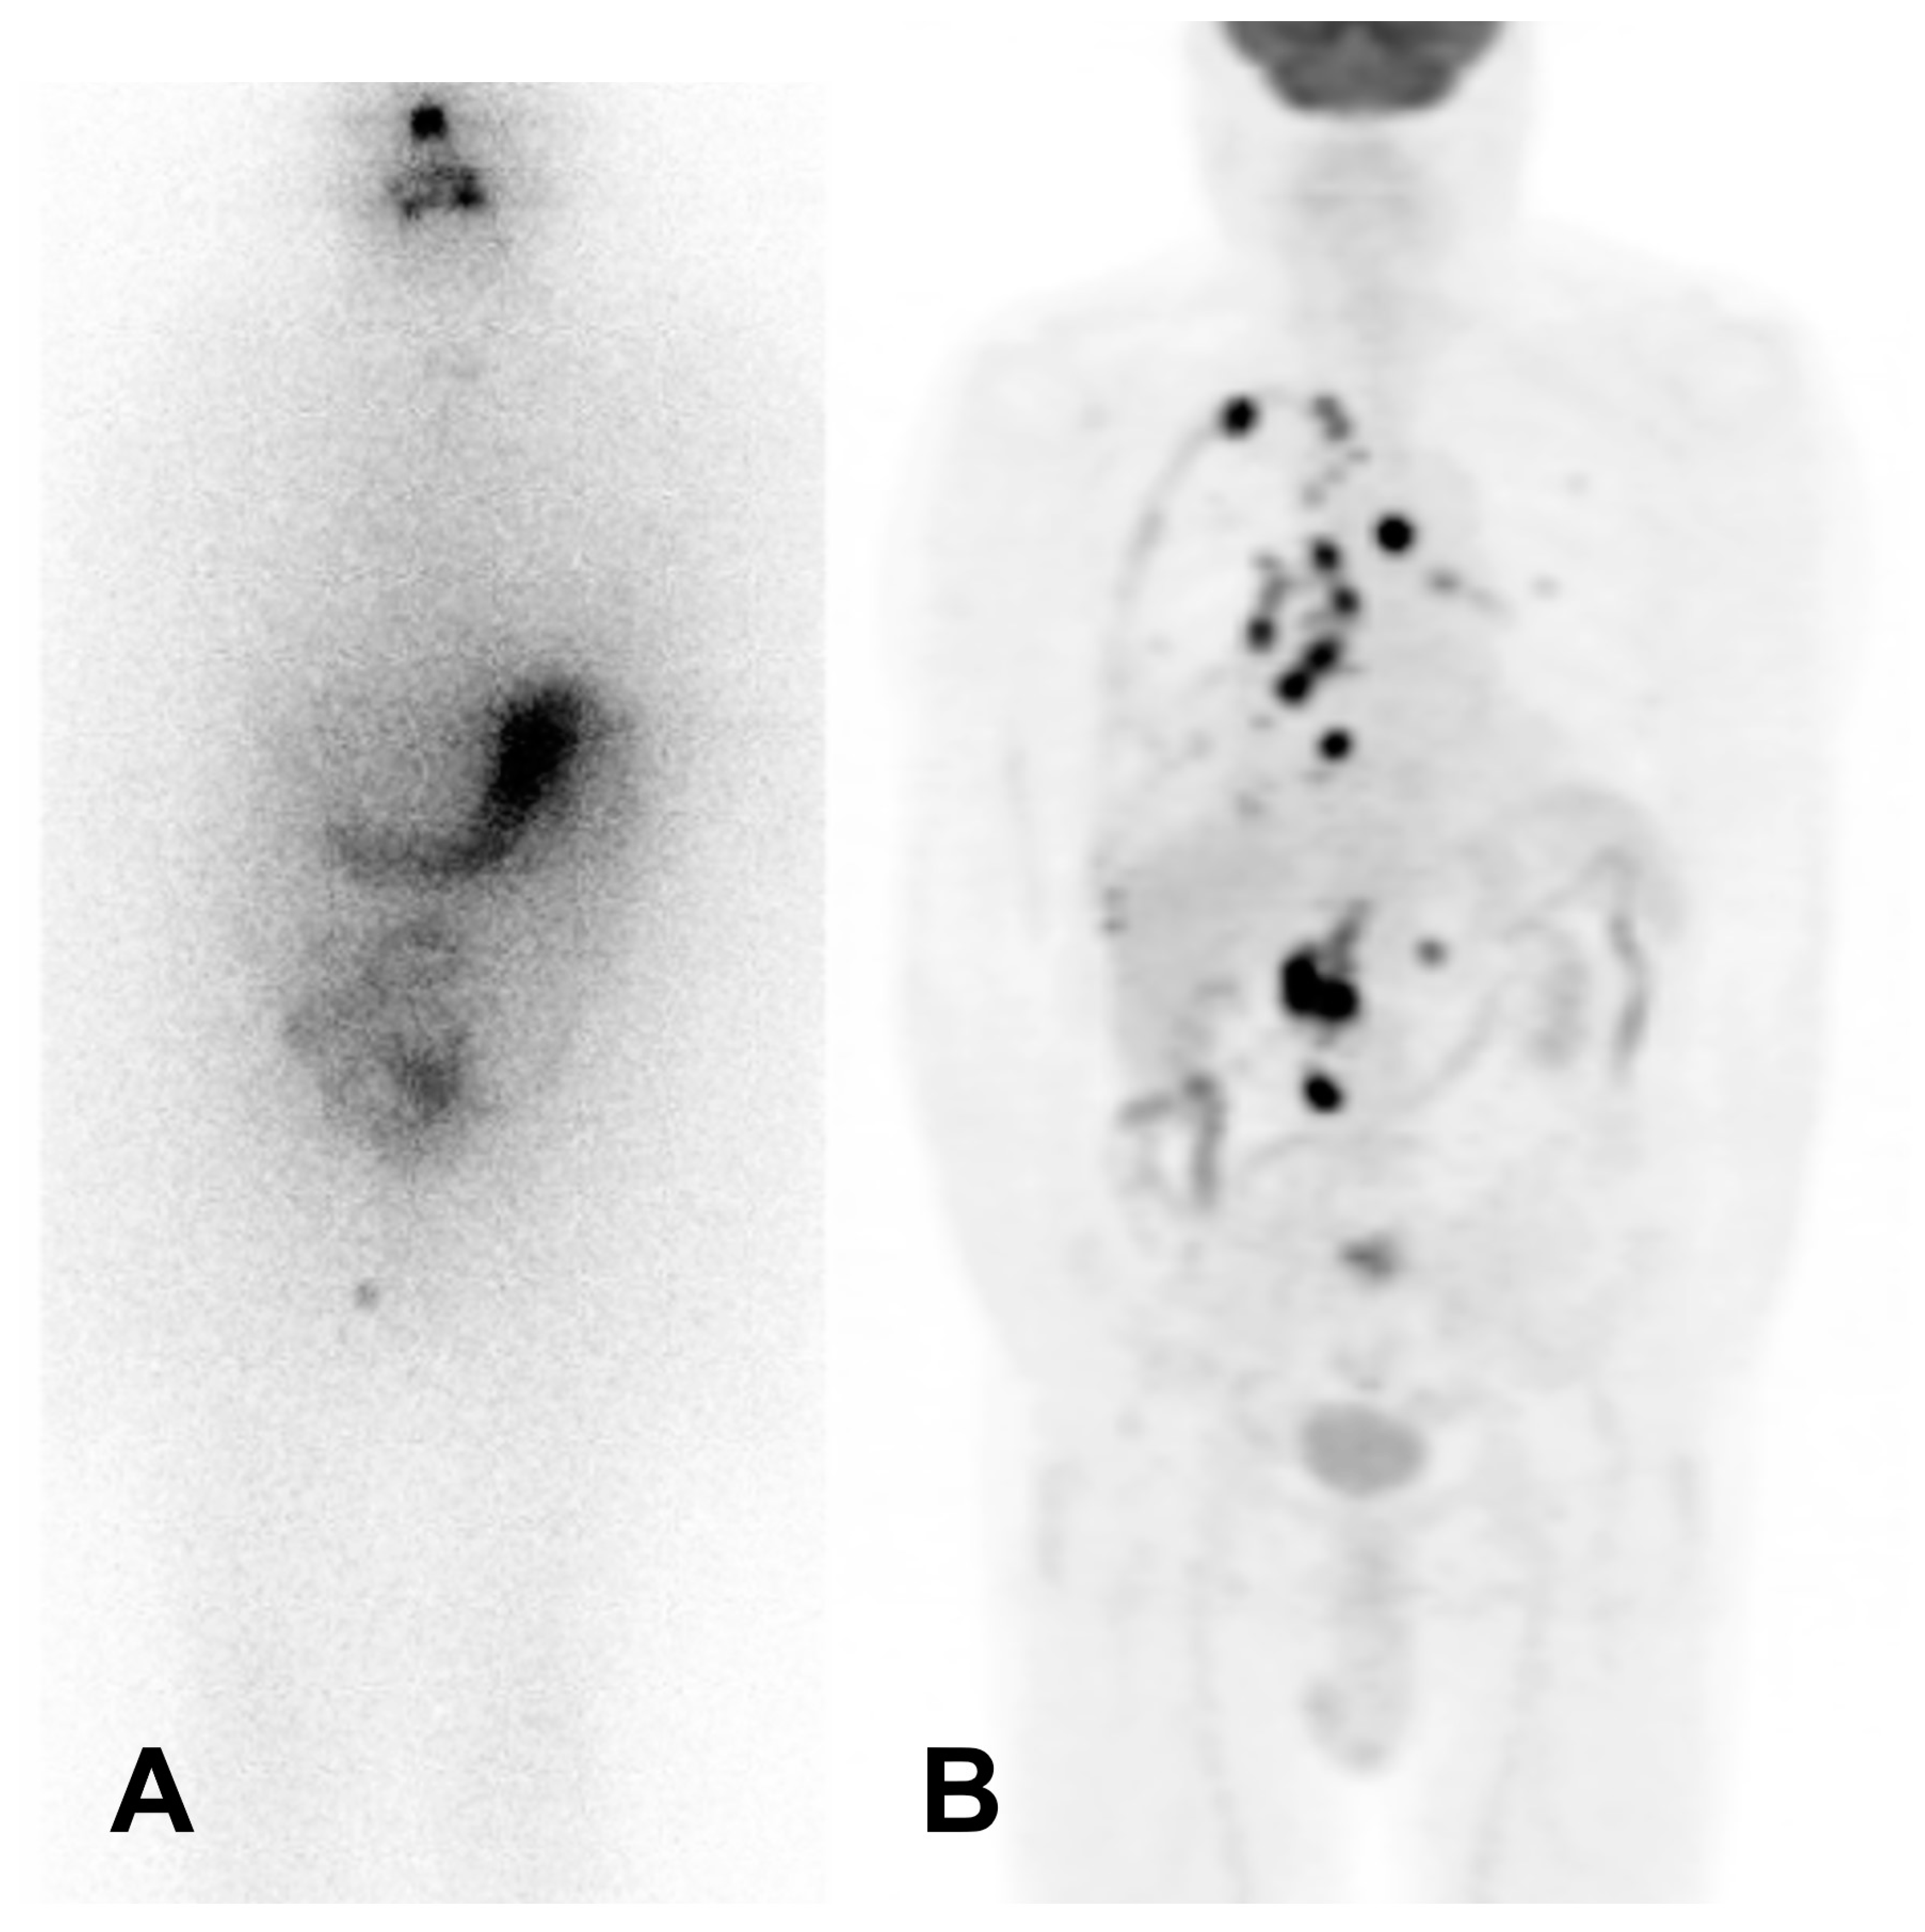

- Hadad, B.; Askari, E.; Zakavi, S.R.; Aryana, K.; Erfani, S.; Sahafi, P.; Nabavi, N.; Aghaee, A. Case Report: Regaining Radioiodine Uptake Following PRRT in Radioiodine-Refractory Thyroid Cancer: A New Re-Differentiation Strategy? Front. Nucl. Med. 2022, 2, 1071022. [Google Scholar] [CrossRef]